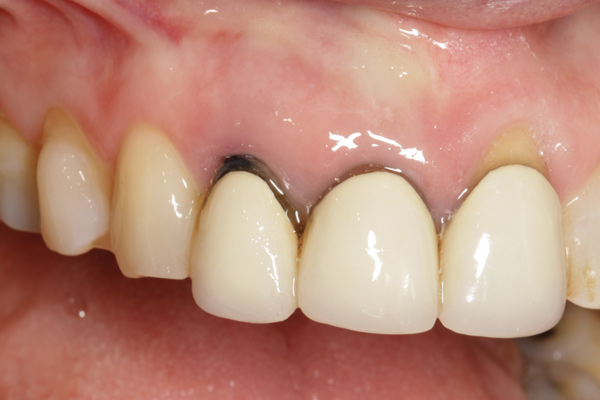

To predict peri-implant esthetic outcomes, Kois described five essential diagnostic keys that need to be assessed before removing a periodontally hopeless tooth (Figure 3 and Figure 4): (1) relative tooth position; (2) form of the periodontium; (3) periodontal biotype; (4) tooth shape; and (5) position of the osseous crest. Failing teeth that have a thick, flat gingival biotype, are square shaped, and have < 3 mm vertical distance from the position of the facial and interproximal crest have the lowest risk of developing recessions after implant placement.23 Therefore, implant surgery may be performed by either an open flap or flapless approach. However, teeth with a thin soft-tissue biotype, a highly scalloped gingival architecture, and a triangular shape that are positioned facially have less-predictable peri-implant esthetic outcomes. When a tooth presents with these unfavorable anatomical features, grafting procedures should be considered both before and after tooth extraction to prevent vertical loss and facial collapse of the gingival architecture.21 Flapless tooth extraction should be attempted in the esthetic zone to maintain blood supply from the periosteum and endosteum and maximize healing potential (Figure 5).44 In addition, several surgical protocols have been proposed to avoid peri-implant mucosal recessions, including 3-dimensional implant positioning,45,46 the use of platform-switching implants,47,48 and soft-tissue augmentation.8,49,50